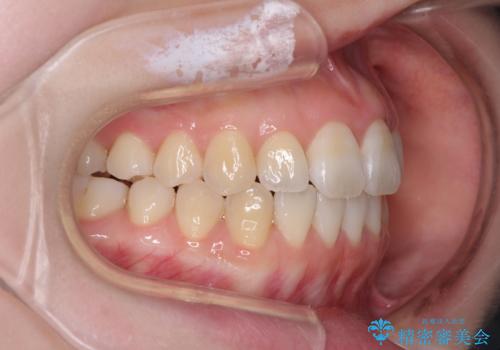

- 前歯の捻れと、ちょっとした出っ張りを気にして来院された患者様です。

歯と歯の間を削る(IPR)ことでデコボコを解消し、インビザラインで整えることとしました。

インビザライン治療特有の奥歯が接触しない時期が続き、当初予定よりも期間がかかりましたが、最終的には安定した咬み合わせと、整った前歯になりました。